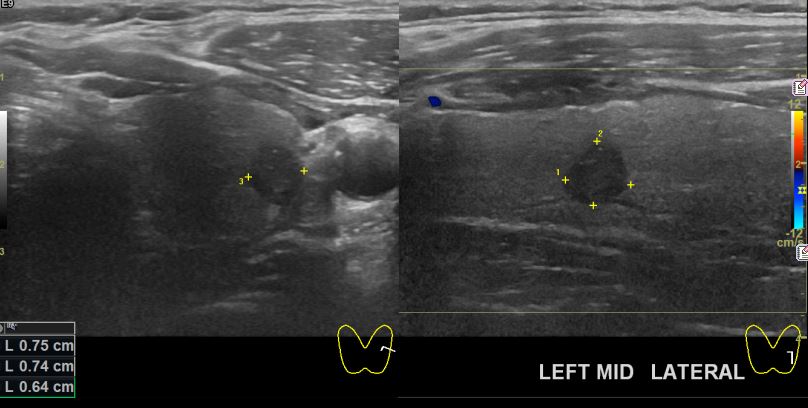

상기환자 건강검진상 이상소견으로 내원하신 50대 남성분으로 좌측 의심스러운혹

세포검사진행후 갑상선암으로 진단되었읍니다